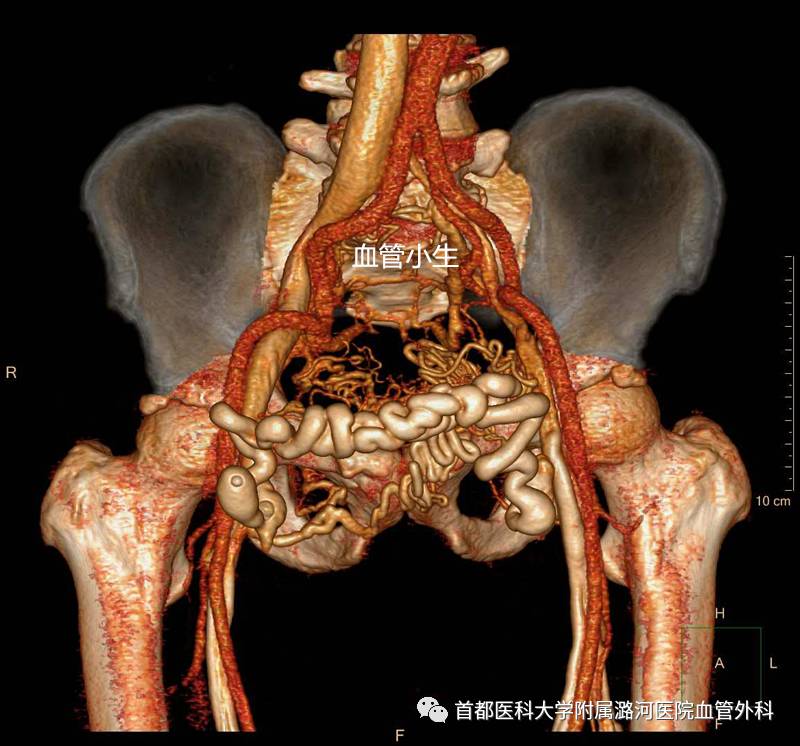

左侧髂总静脉压迫综合征

髂血管解剖特点

左右髂总静脉于第5腰椎体中下部平面右侧汇合成下腔静脉,右侧髂总静脉几乎呈直线与下腔静脉连续,左侧髂总静脉自盆腔横行向右,经腰骶椎前侧,与下腔静脉几乎成直角汇合。腹主动脉相当于4腰椎分出左右髂总动脉,右侧髂总动脉跨越左侧髂总静脉之前方,然后向骨盆右下延伸。左侧髂总静脉在前方受右侧髂总动脉的骑跨,后方受腰骶部生理性前凸的推挤,造成前压后挤。